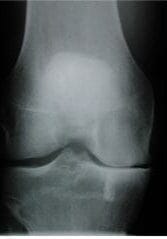

standin-ap-xr-with-med-oa-g

An AP standing x-ray of the knee showing some medial (inner) joint space narrowing.